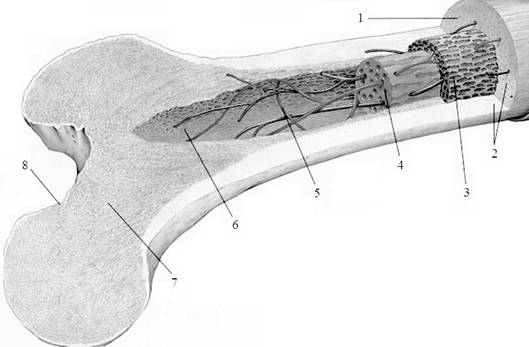

Изучение костного мозга: анатомия и функции